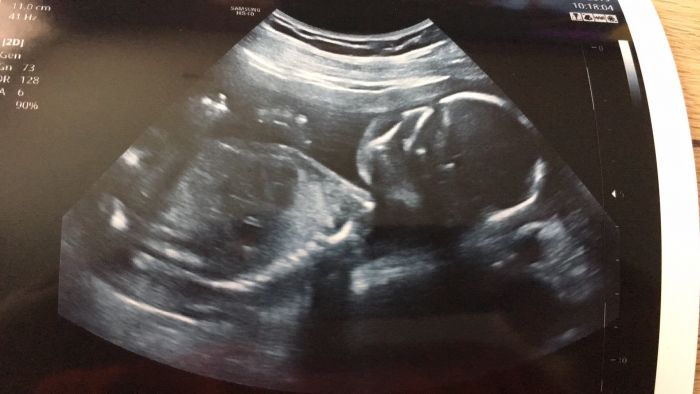

Zdravím :) tak i my máme po velkém ult, akorát miminko se nejspíš stydí, 10 minut se pan doktor snažil zjistit pohlaví, a miminko ne a ne ukázat. Nakonec si mezi nožičky strčilo obě ručičky a byl konec :D. Další kontrolu máme až 25.7 tak snad se na příští kontrole ukáže, jelikož už chceme s manželem kupovat nějaké věci. Je to naše první mimi. Jinak já mám od početí až do teď (21tt) pořad stejnou váhu. Jím na co mám chuť :). Já se taky každý večer po koupeli mažu (bo-oilem), tak uvidím zda to pomůže či nikoliv. Přikládam foto :)